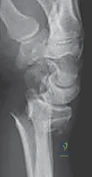

الأعراض والعلامات السريرية

يتعرف المريض والطبيب على كسر الكعبرة البعيدة من خلال مجموعة من العلامات السريرية الواضحة:

* ألم حاد ومفاجئ: يتركز في منطقة الرسغ ويزداد بشدة عند محاولة تحريك اليد أو الأصابع.

* تورم سريع وكدمات: تظهر حول الرسغ وقد تمتد إلى الأصابع أو الساعد.

* تشوه شكل الرسغ: يُعرف كلاسيكياً بـ "تشوه ظهر الشوكة" (Dinner Fork Deformity)، حيث ينزاح الجزء المكسور من الكعبرة نحو الخلف (الناحية الظهرية)، مما يعطي الرسغ شكلاً يشبه ظهر الشوكة.

* خدر وتنميل: في بعض الحالات، قد يضغط الكسر والتورم على العصب الأوسط (Median Nerve)، مما يسبب أعراضاً مشابهة لمتلازمة النفق الرسغي.